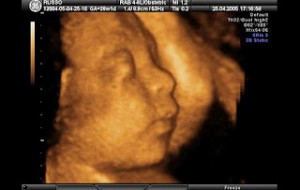

Hamileliğin (Gebeliğin) 35. Haftası Resim ve Video;

Bebeğin Boyutu: 43.7 cm, 1.9 kg

Çocuğun gelişimi: akciğerler alveollerin genişlenmesini sağlayacak ve doğduktan sonra bebeğinizin nefes alması için önemli olan surfaktan (Surfaktan maddeler en basit tanımı ile bir sıvının yüzey gerilimini azaltan maddelerdir) üretiyor.

Böbrekler tamamen gelişmiştir.

Bu haftadan itibaren artık bebek rahim içerisinde oldukça fazla yer kaplar ve bu yüzden ona hareket edecek fazla alan kalmaz. Eğer bebeğinizin hareketlerinde azalma his ederseniz endişe etmeyin, hareketlerin azalması bu yüzdendir.